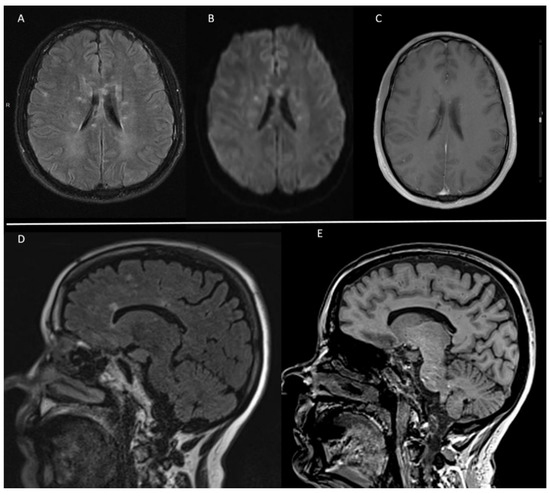

| MRI | Callosal, periventricular, supratentorial grey matter pontine | Callosal, periventricular | Callosal, periventricular, supratentorial grey matter, basal ganglia, cerebellum, brainstem, perivascular and leptomeningeal contrast uptake | Callosal periventricular, basal ganglia | Callosal | Callosal, periventricular, subcortical cerebellum | Callosal periventricular, subcortical | Callosal, periventricular, centrum semiovale pontine, necrotic lesion on corona radiata | Callosal, periventricular, subcortical, basal ganglia, internal capsule, cerebellum |